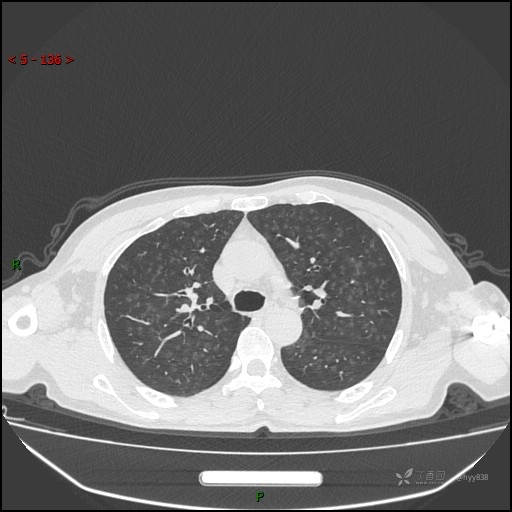

呼吸科电话会诊病例:过敏性肺炎 VS 吸烟相关间质性肺炎 VS 尘肺……结果公布~

性别:男

年龄:55岁

简要病史:渐进性呼吸困难。

胸部CT平扫

电焊工尘肺 (2)